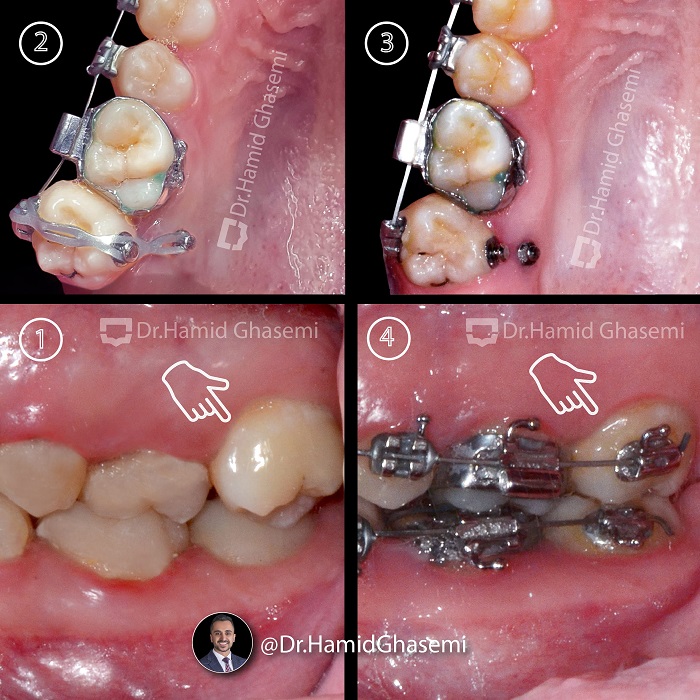

ارتودنسی دندان نهفته؛ راهحلی برای درمان مشکلات پنهان دندانها10 آذر 1403 - 6:20 ب.ظ